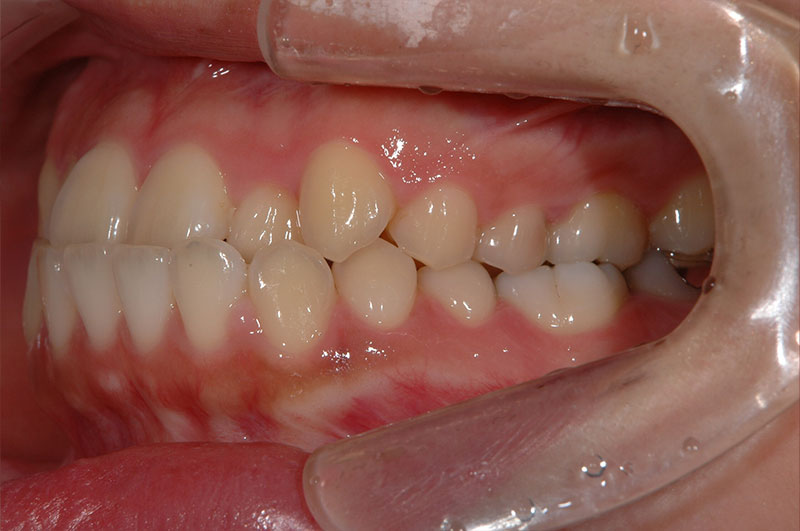

今回は反対咬合に対して、外科手術を行わずに矯正治療のみで改善した成人の症例をご紹介します。

「反対咬合=手術が必要」と思われがちですが、噛み合わせの状態によっては、今回のように矯正治療だけで改善が可能なケースもあります。

治療前後の変化を実際の症例写真でご覧いただくことで、

反対咬合がどのように改善するのかを、イメージしていただければと思います。

症例の概要(手術なし・成人の反対咬合)

術前

術後

| 主訴 | 反対咬合 |

| 初診時年齢 | 24歳 |

| 治療内容・使用した装置 | 頬側ブラケットを用いた永久歯全体の矯正治療、アンカースクリュー |

| 抜歯の有無 | 左右下顎第一小臼歯、左側上顎第二小臼歯抜歯 |

| 治療期間 | 約24ヶ月 |

| 費用 | 総額819,500円(税込) (相談料、検査料、診断料、動的治療費、抜歯費、アンカースクリュー埋入、除去費、保定期間料等含む) |

| 治療に伴うリスク・副作用 | 歯の移動に伴う痛み、上下顎前部の歯根吸収、装置による口内炎、ブラッシング不良によるむし歯、歯周炎 |